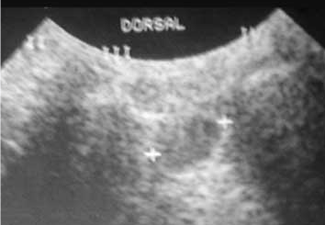

Diagnóstico de neuroma de Morton por ecografía dinámica.